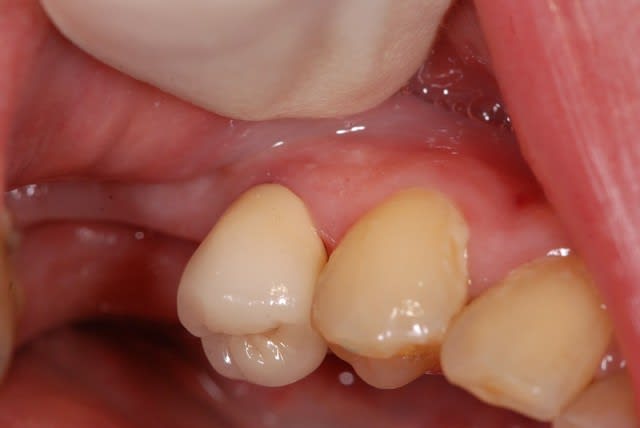

Regardez ce que je viens de recevoir de mon prothésiste habituel.

Vous conviendrez que le résultat n'est pas terrible, mais est assez représentatif de ce que je reçois.

A chaque fois, je met en cause mes piètres talents de prise de teinte, mais vous constaterez sur la deuxième photo que j'étais quand même plus proche que lui.

Alors est-ce qu'on arrive aux limites des CCM ?

Ou faut-il que je change de prothésiste (suggestions sur Paris/RP en MP, merci) ?

'tain là on est dans le B1 en plus elle est hyper opaque

"" Alors est-ce qu'on arrive aux limites des CCM ? ""

des CCM non, mais celles de ton prothé ça a l'air ^^

Le teintier que je présente est un A3,5.

Merci de me confirmer que je ne suis pas un chieur...

Au niveau opacité c'est à peu près ce que j'ai régulièrement.

Je me disais, pour du moyen-haut de gamme, tu ne peux pas avoir la lune. Vos 45 euros sont très éloignés du prix payé.

c'est une ccm monocouche avec un peu de maquillage au collet ,maqquillage qui finira par s'en aller..

trop globuleuse et epaisse (maisquelle epaaisseur lui as tu laissé?)

et pas très bien sculptée(mais qu'y a t'il en face?)